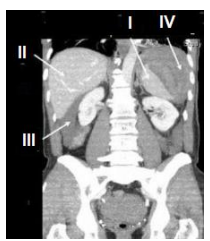

Observe a imagem radiológica abaixo:

Fonte: https://www.lecturio.com/pt/concepts/imagem-do-baco/

Os números I, II, III e IV refere-se a quais órgãos?